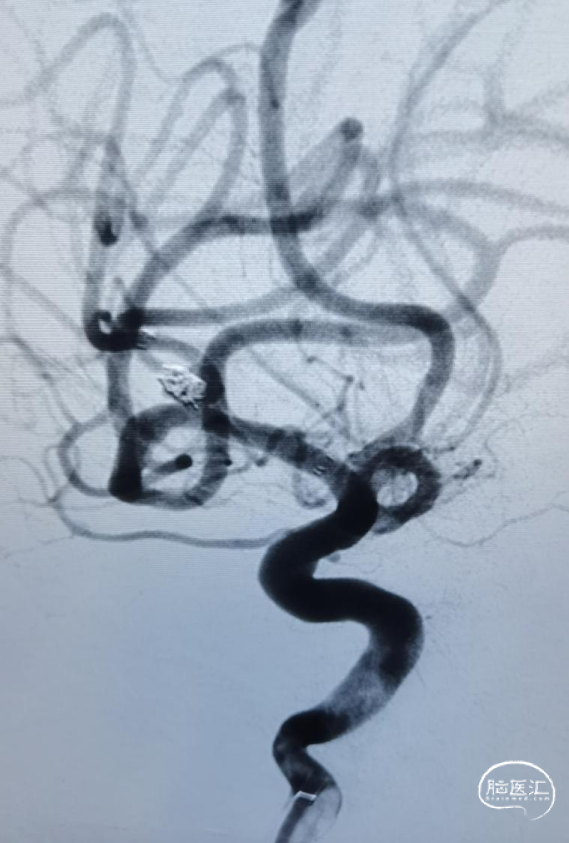

术前影像

CT显示广泛蛛网膜下腔出血,右侧侧裂池为著。

DSA示:右侧大脑中动脉分叉上干起始部宽颈动脉瘤,呈不规则分叶状,载瘤动脉管径纤细,角度锐利,载瘤动脉直径1.45mm,大脑中动脉直径2.26mm,动脉瘤大小约5.35mm×3.98mm×4.14mm。